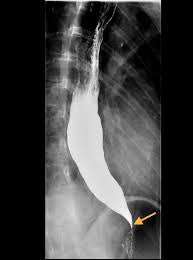

السلام عليكم و رحمة الله و بركاته. نسلط الضوء اليوم على مشكلة البلع بسبب مرض #اكاليزيا او #achalsia و الناتجة عن عدم قدرة صمام المريء السفلي على الارتخاء بتاتا بالاضافة الى فقد المريء قدرته على الانقباض و دفع الطعام الى الاسفل باتجاه المعدة مما يؤدي الى تجمعه في المريء

تسبب هذه الحالة تجمع الطعام في المريء و منعه من العبور الى المعدة لهضمه و من ثم امتصاصه. يؤدي ذلك الى شعور المريض بعدة اعراض منها: صعوبة البلع، الام الصدر، الغثيان و الاستفراغ، نزول الوزن، السعال و التهابات الرئة المتكررة بسبب استنشاق الطعام المرتجع من المريء و الحرقان.

يتم تشخيص المشكلة اولا عن طريق اشتباه الاصابة بالمرض من خلال الاعراض المذكورة انفا و من ثم التاكد من التشخيص بواسطة منظار المعدة، صبغة الباريوم و اخيرا اجراء فحص جهد المريء و المعروف ب manometry

هذه صور لاحدى الحالات التي اجريت في المستشفى الجامعي و التي بحمد الله تكللت بالنجاح بواسطة المنظار عن طريق اجراء فتحة صغيرة لا تتجاوز ٢ سم في المريء.